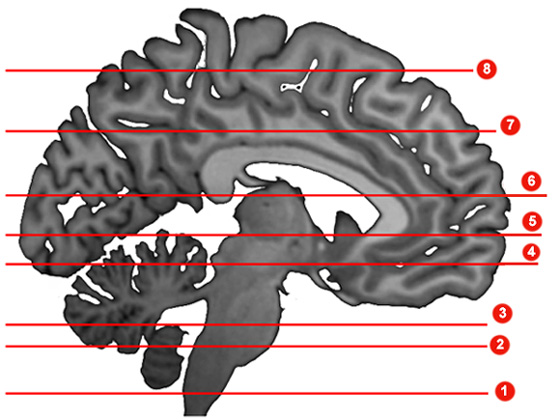

Parkinson's Disease is characterized by a loss of cells in a specific area of the brainstem. Select the level of brainstem in which you would normally find the cell bodies of these neurons.